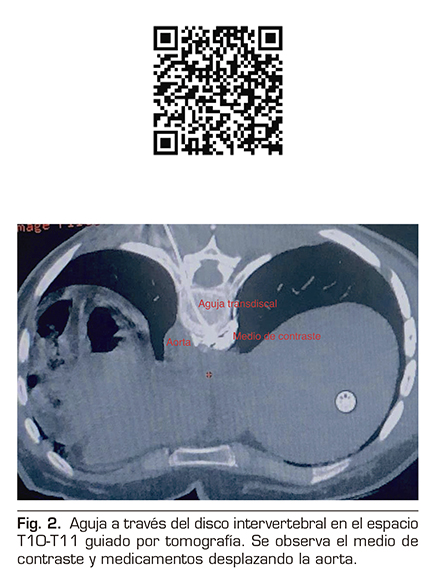

Se realizó un abordaje transdiscal de los nervios esplácnicos a nivel de T10-T11 guiado por tomografía.

Con la paciente en decúbito prono se identificó el espacio seleccionado, se infiltró lidocaína al 1 % a 5 cm de la línea media izquierda y se avanzó una aguja espinal número 22 progresivamente, realizando cortes topográficos hasta alcanzar el retromediastino. Se confirmó la punta de la aguja con 2 ml de medio de contraste iopromida 300 mg/ml (Ultravist®), y se procedió a inyectar bupivacaína 0,5 % más metilprednisolona 80 mg para un total de 10 ml (Figura 2).

Además, se debería tener siempre presente el manejo intervencionista del dolor cuando los fármacos no brindan analgesia efectiva o producen efectos adversos importantes, ya que constituye un escalón más de la escalera analgésica de la OMS, y se convierte en un importante recurso (16), como lo fue en este caso, donde se realizó un bloqueo de los nervios esplácnicos guiado por tomografía que ofreció gran resolución espacial y ubicación exacta de la punta de la aguja en la reconstrucción 3D. La vía transdiscal fue elegida por ser la técnica que mejor manejamos al ser alumnos directos de quien la ideó (2); teóricamente, por su acceso puede disminuir el riesgo de complicaciones como paraplejia, neumotórax y perforación hepática o renal, sobre todo en pacientes con anatomía modificada. Asimismo, al ser un bloqueo retrocrural nos ofrece una importante barrera anatómica vs. el bloqueo del plexo celiaco (17).